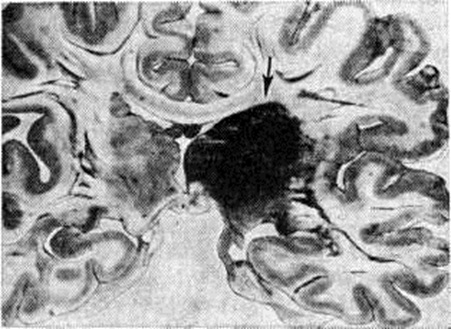

Геморрагический инсульт, как правило, возникает при заболеваниях, протекающих с повышенным артериальное давление. Это обусловлено тем, что сосудистые кризы (смотри полный свод знаний), характерные для гипертонической болезни (смотри полный свод знаний) и артериальной гипертензии (смотри полный свод знаний Гипертензия артериальная), приводят к морфологический изменениям стенок внутримозговых сосудов с нарушением их проницаемости — плазматическому пропитыванию (рисунок 1), некрозам (рисунок 2), образованию микроаневризм (рисунок 3) и их разрывам. Разрыв врождённых артериальных и артериовенозных аневризм может протекать на фоне нормального давления. Преимущественная локализация и характер геморрагий определяются особенностями ангиоархитектоники различных отделов мозга. При гипертонической болезни наиболее тяжёлым изменениям подвергаются сосуды подкорковых узлов и зрительного бугра. Это объясняется отхождением глубоких ветвей под прямым углом от средней мозговой артерии, являющейся продолжением внутренней сонной артерии, и незначительным числом анастомозов сосудов в этой области. В связи с этим на вскрытии кровоизлияния наиболее часто (40%) обнаруживаются в подкорковых узлах с распространением в прилежащее белое вещество (так называемый латеральные кровоизлияния, то есть расположенные латерально от внутренней капсулы, рисунок 4). Второе место по частоте (16%) занимают обширные кровоизлияния, разрушающие подкорковые узлы, внутреннюю капсулу, зрительный бугор (так называемый смешанные кровоизлияния — рисунок 5). Кровоизлияния в зрительный бугор (так называемый медиальные — рисунок 6) составляют 10%, в мозжечок — 6—10%, в мост мозга — 5% от общего числа внутримозговых геморрагий. Кровоизлияния только в белое вещество полушарий мозга встречаются крайне редко. Подразделение полушарных кровоизлияний на латеральные, медиальные и смешанные имеет особое значение в связи с хирургическим лечением геморрагического Инсульт.

Рис. 5. | ||